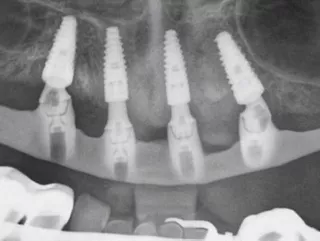

Edentulous maxilla with limited bone height in the posterior region. Flapless guided surgery, placement of two Straumann® BLC implants ∅ 3.75 x 10 mm (at positions 12 and 22) and two Straumann® BLC implants ∅ 4.5 x 10 mm (at positions 14 and 24). Immediate fixed temporization was achieved using the patientʼs former denture, which remained in function for three months. Subsequently, considering the patientʼs presentation with a thin upper lip, high smile line, and vertical bone crest atrophy, a final metal-reinforced overdenture fixed on a Dolder bar was selected.

• Panoramic X-ray done for Sheffield test approval.